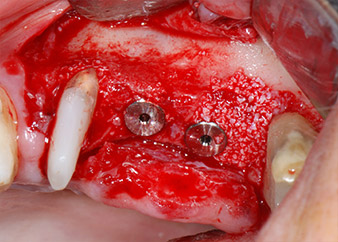

IImplant beds were prepared at sites 25 and 26 with rotary instruments, used in a contra-angle handpiece with a 20 : 1 transmission ratio with an updated powerful implant motor (Implantmed, W&H) (Fig. 8).

The implants (Restore, Keystone Dental, diameter 3,75 mm, length 8.0 mm) were placed with the implant motor (Figs. 11 and 12).